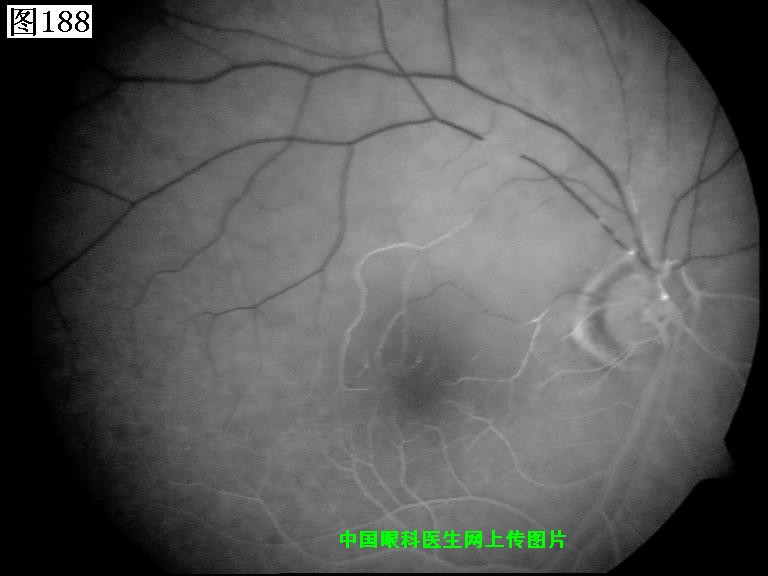

185 186 187 188